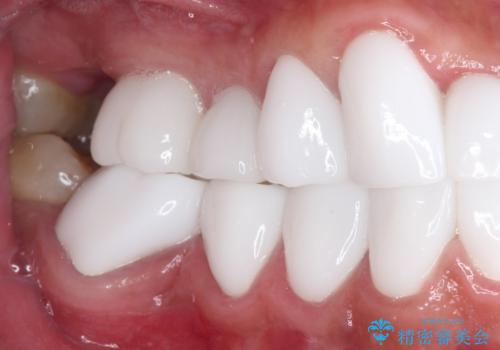

本来、あまりにも不自然な歯となるため、フルジルコニアクラウンを前歯に使用することは、咬合力が強すぎる場合を除き、ほとんどありません。

それでも、色調、形態ともに不自然なくらい真っ白な歯をご希望でしたので、患者様には大変満足していただきました。